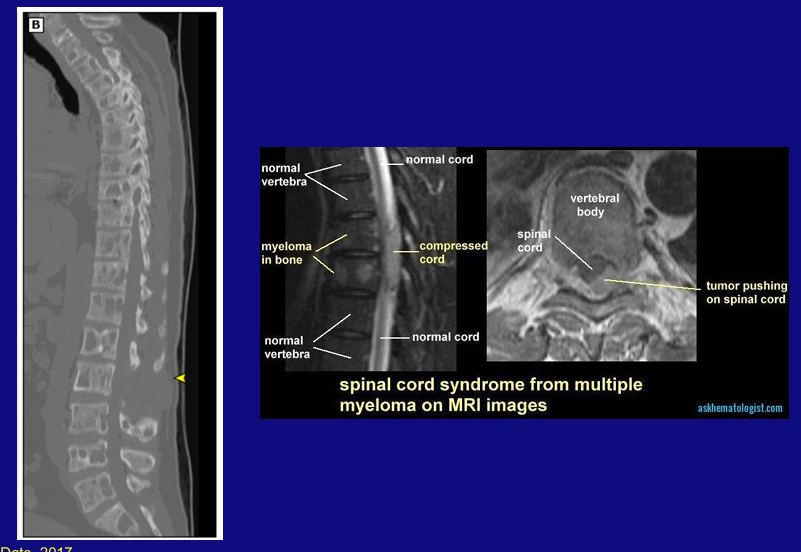

spinal cord syndrome